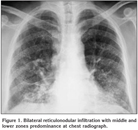

On physical examination oculocutaneous albinism, strabismus, nystagmus, clubbing and bilateral inspiratory rales were detected. The temperature was normal, the blood pressure 100/60 mmHg, the pulse 112 beats per minute and the respiratory rate 28 breaths per minute. Laboratory studies revealed a normal complete blood count and serum biochemistry. The prothrombin time, partial-thromboplastin time and international normalized ratio were in normal range, however, the bleeding time was prolonged (14 minutes; normal: 2-9 minutes). Chest radiograph showed bilateral reticulonodular infiltration with middle and lower zones predominance (Figure 1). A thorax computed tomography (CT) revealed bilateral diffuse interlobular septal thickness and traction bronchiectasis which were more prominent in the basal segments of lower lobes and also a honeycomb pattern (Figure 2). The oxygen saturation was 66% while the patient was breathing ambient air and arterial blood gas analyses revealed severe hypoxemia with a PaO2 value of 36.7 mmHg. Accordingly, oxygen therapy was initiated. Since supplemental oxygen by nasal cannula failed to increase the oxygen saturation above 90%, oxygen was given by a face mask with reservoir bag. During follow-up, although pirfenidone therapy was planned, clinical deteroriation developed and the patient died at the 14th day of hospitalization because of the respiratory failure.

Figure 1

The radiologic appearance of pulmonary fibrosis in HPS is comparable to that of idiopathic pulmonary fibrosis and the predominant radiologic pattern is interstitial patterns or infiltrates that usually involve both lungs symmetrically as in our case.